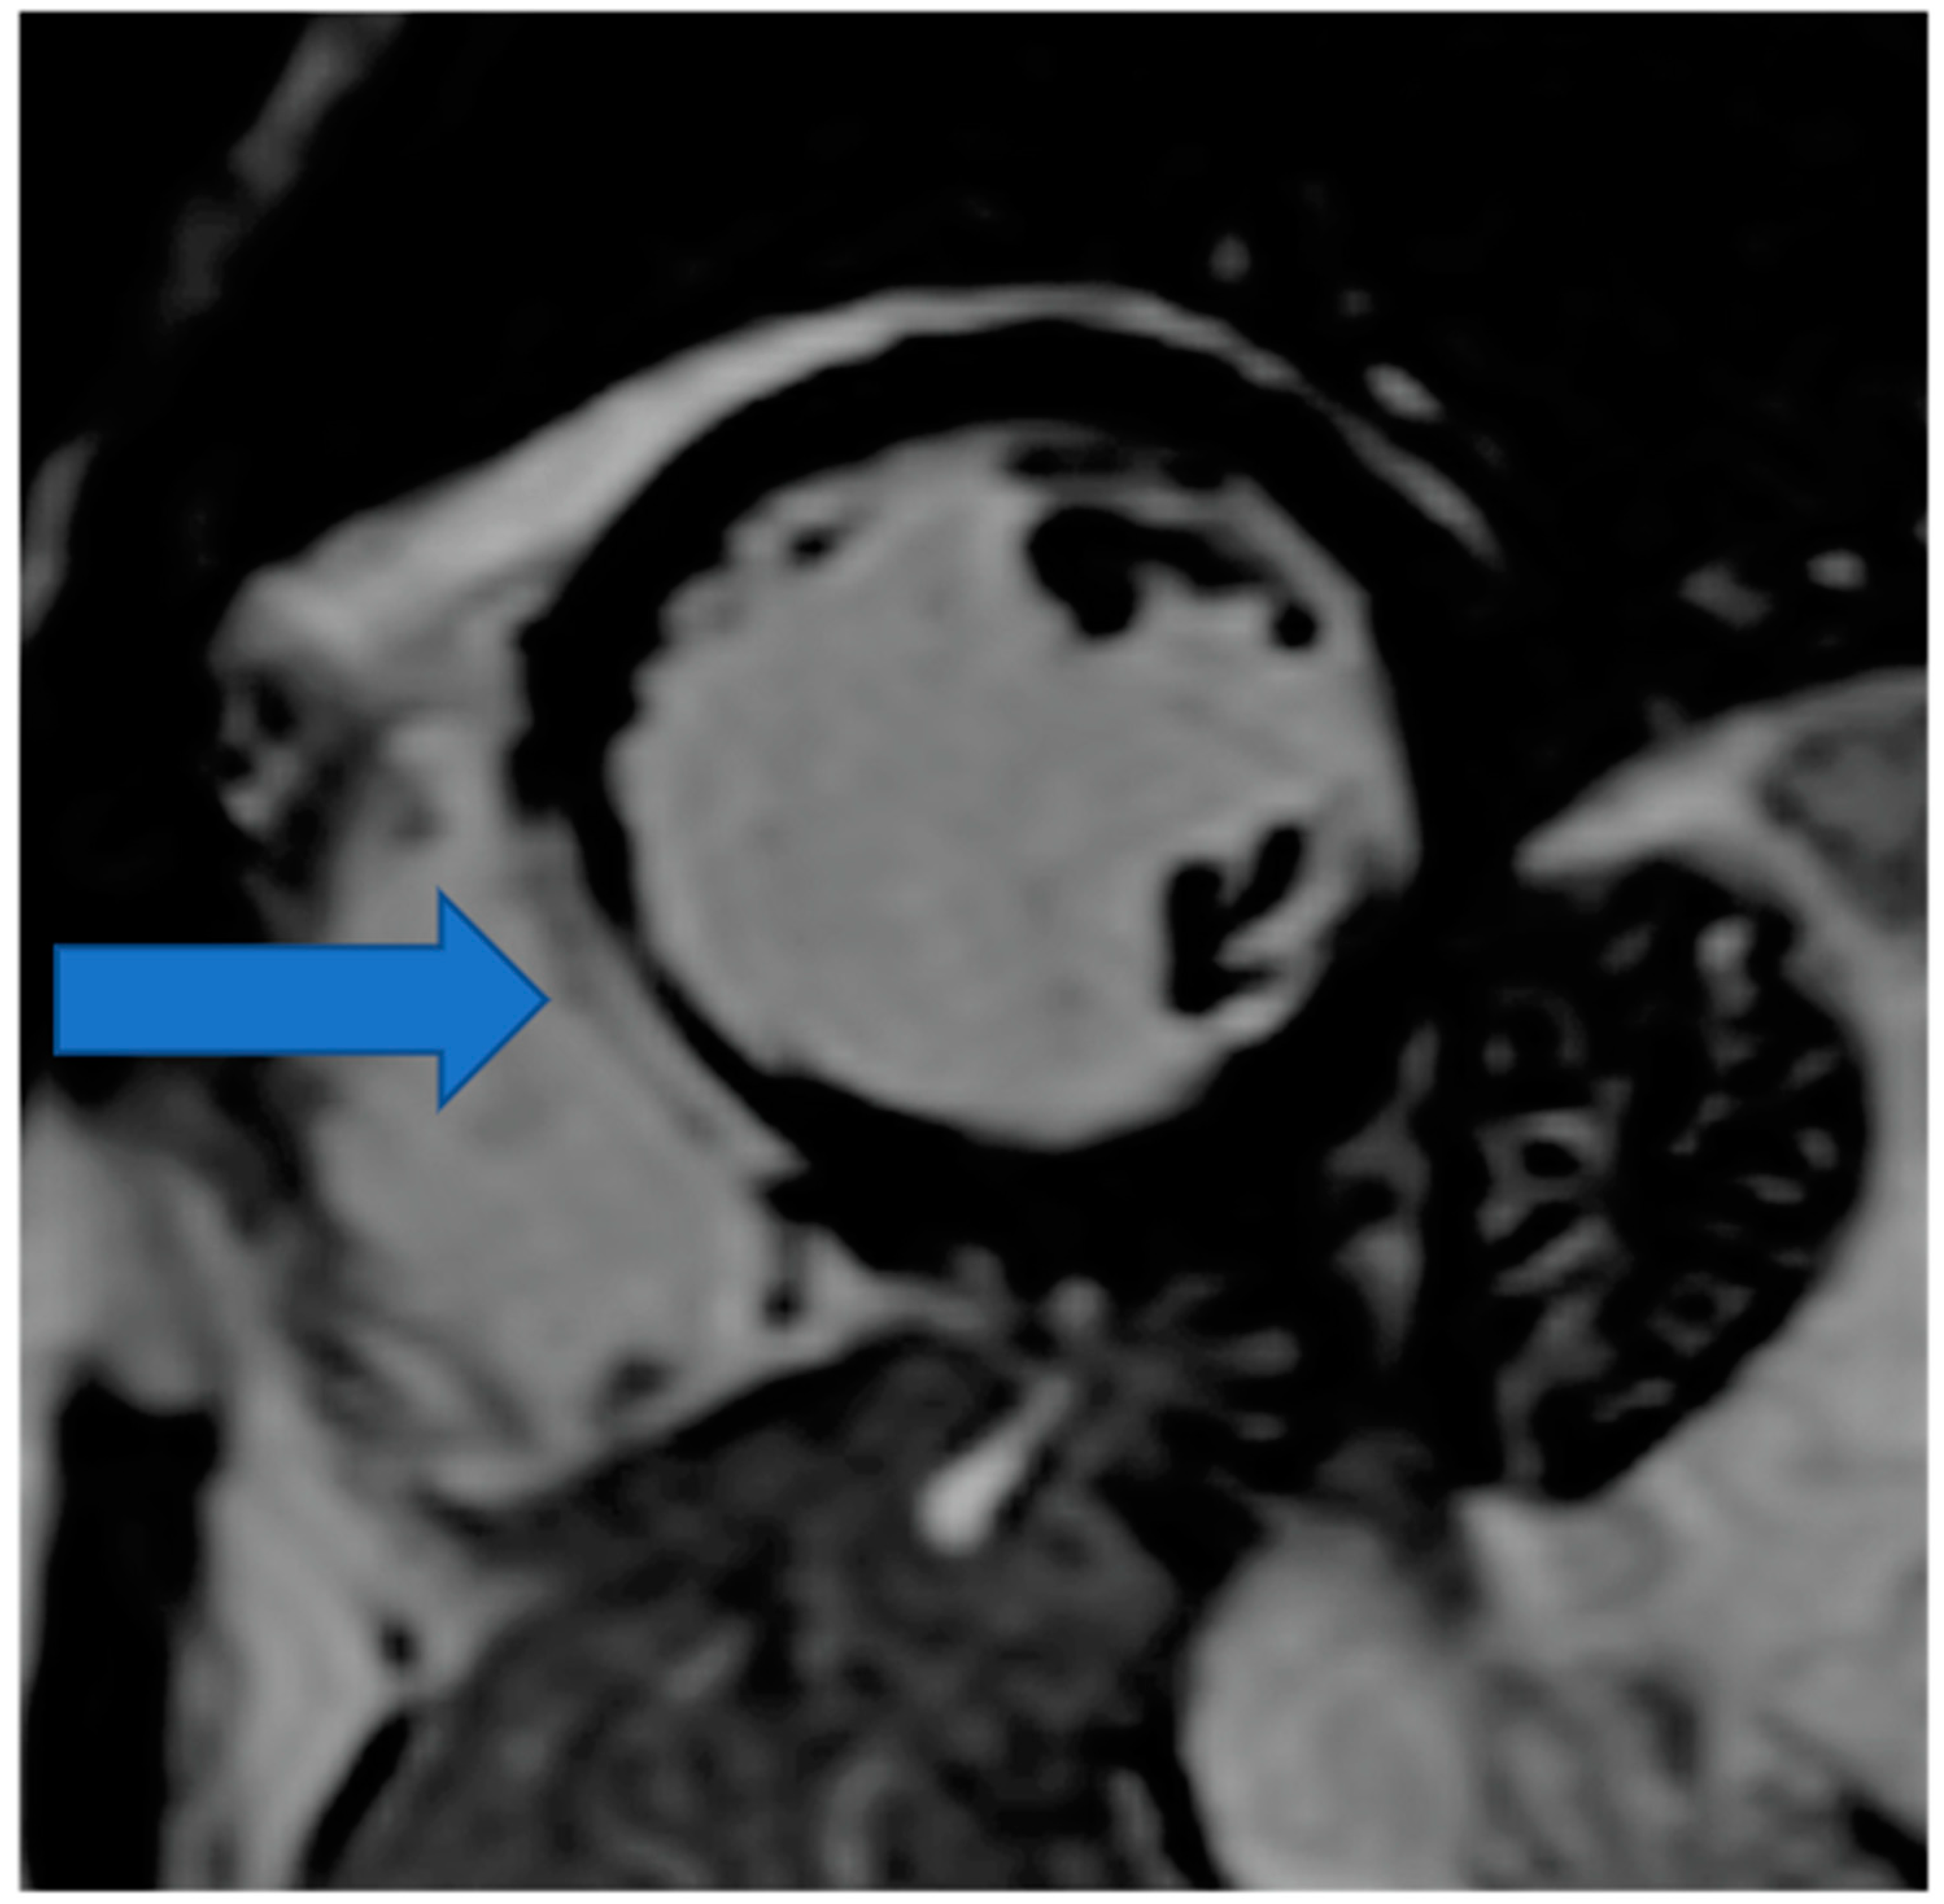

4.3. Myocardial Ischemia Assessment